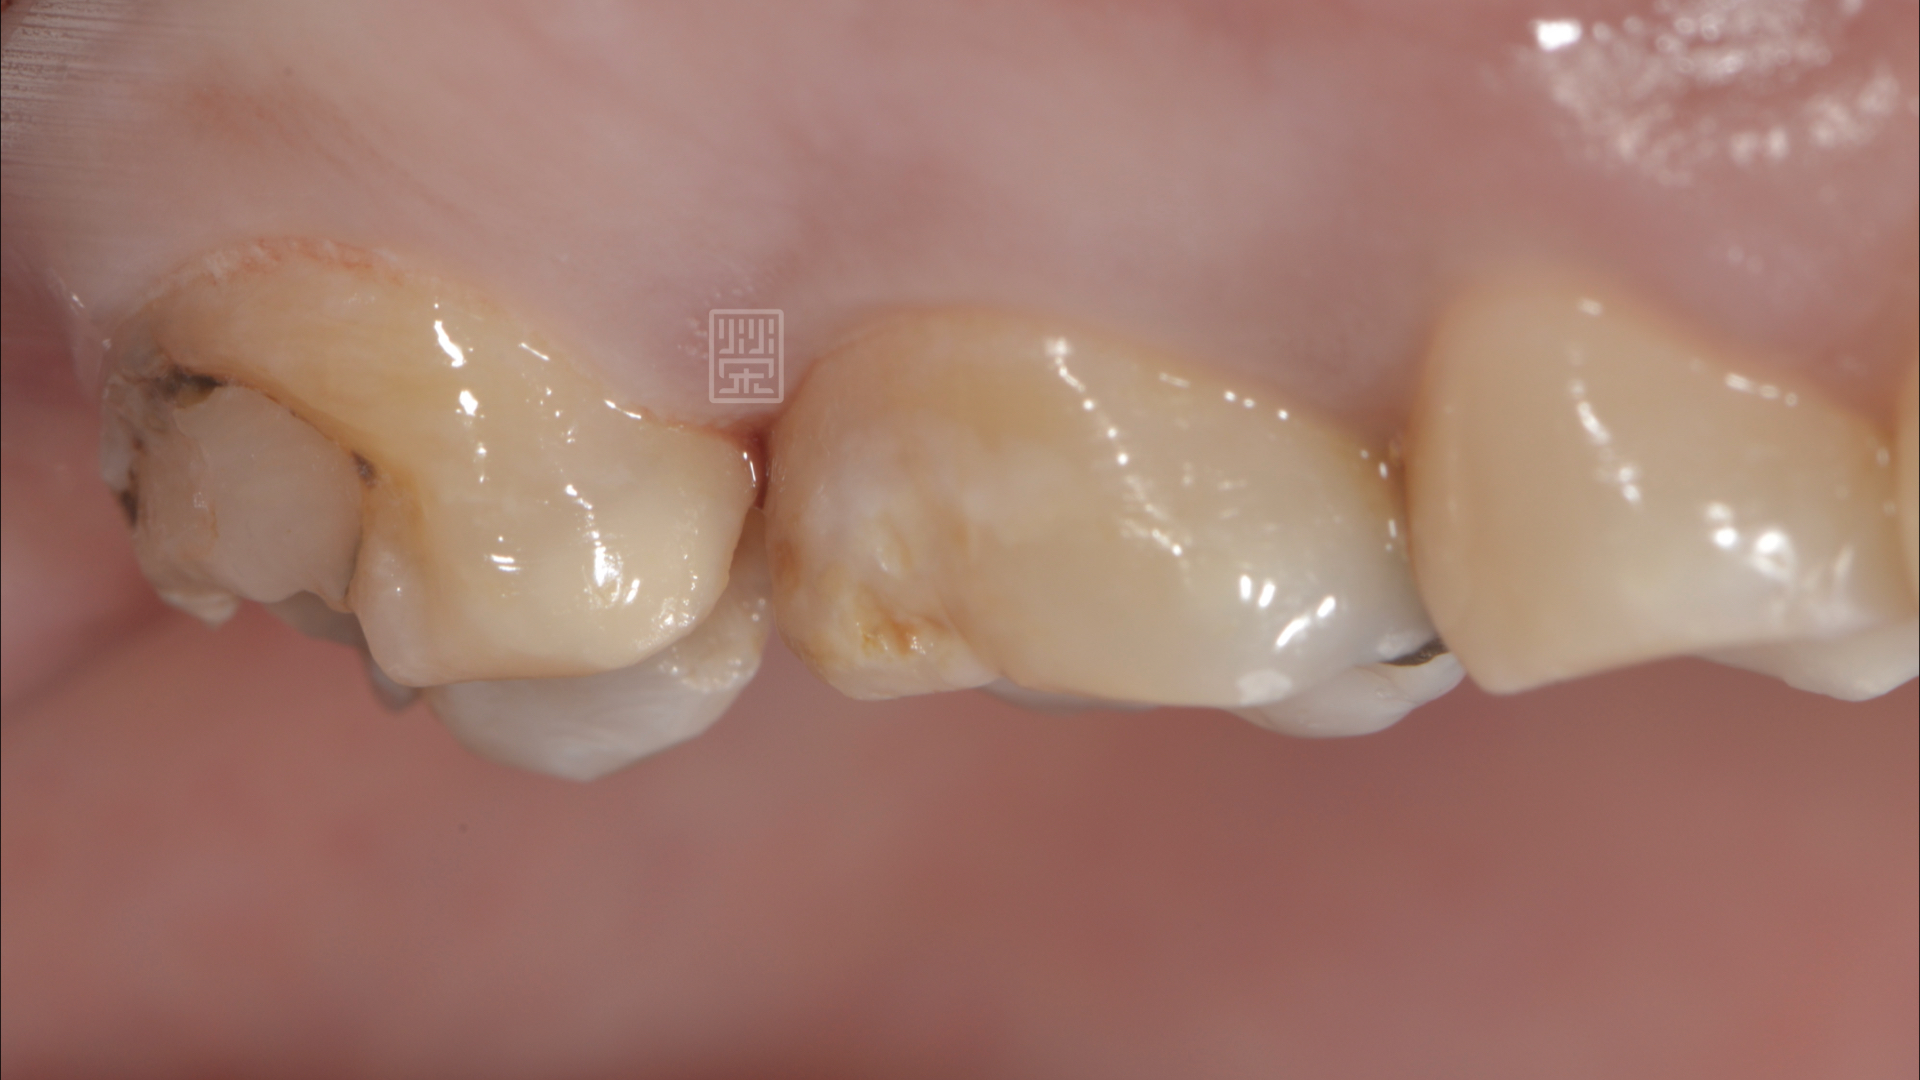

修形後

經由診斷後,應該是蛀牙造成牙齒損傷,咬到硬物,牙齒斷裂,幸運的是,牙齒神經依然健康,只是牙齒齒質受損嚴重,

在清除蛀牙、舊的填補誤之後,利用全瓷黏著贋復物,恢復型態與功能,讓陳小姐能夠自在的享用美食。